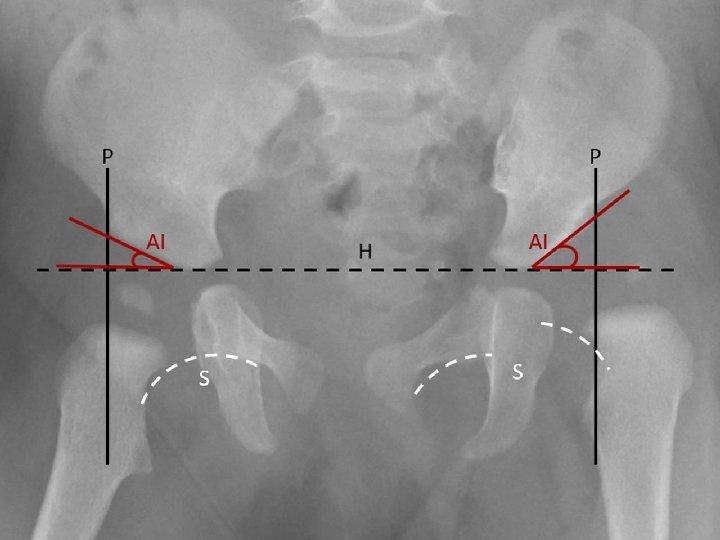

Plain Radiography From AP radiograph of the hip Hilgenreiner line : Horizontal line is drawn between each triradiate cartilage Perkin line: Lines Perpendicular to H line are drawn through the outer edge of the acetabulum (Perkin line), dividing the hip into 4 quadrants - Normally femur head lies in the lower inner quadrant Acetabular index or angle : H line and second line which extend from inner to outer edge of acetabulum -Normally less than 30 degree after age 6 months Shenton’s line : imaginary curved line drawn along the inferior border of the superior pubic ramus and along the inferomedial border of the neck of the femur. - Normally it’s smooth semicircular with no interruption